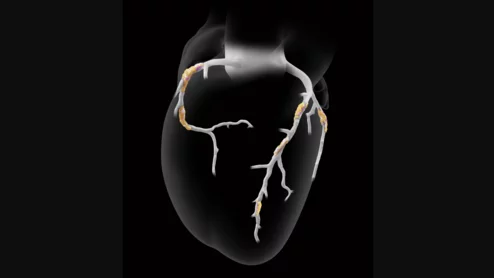

Heartflow Plaque Analysis

It is critical for organizations to have a firm understanding of the CMS 2026 Final Rule to bolster reimbursement, plan service lines and ensure continued access to CCTA, FFR-CT and AI-enabled plaque analysis.